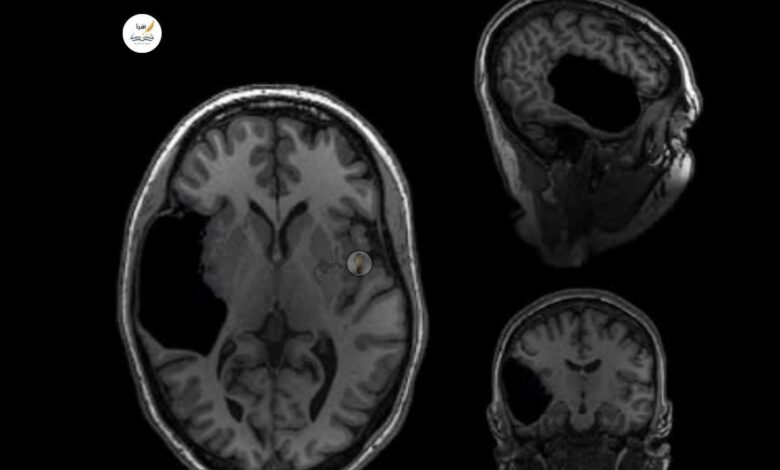

بعد خضوعها لفحص الرنين المغناطيسي، اكتشف الأطباء أنها ولدت دون مخيخ بالكامل — وهو الجزء الخلفي من الدماغ المسؤول عن التوازن، التحكم الحركي، وبعض الوظائف الإدراكية.

تُعرف هذه الحالة باسم غياب المخيخ الخلقي (Cerebellar Agenesis)، ولم يُسجَّل منها سوى تسع حالات حيّة فقط حول العالم.

أظهرت الفحوص أن دماغها أعاد تنظيم نفسه لتعويض غياب هذا الجزء الحيوي، إذ تولّت مناطق أخرى أداء بعض وظائف المخيخ من خلال ما يُعرف بـ المرونة العصبية (Neuroplasticity) — وهي قدرة الدماغ المذهلة على التكيّف وإعادة توزيع المهام العصبية.